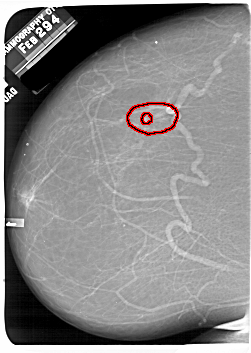

A_1701_1.LEFT_MLO

LEFT_MLO LINES 6841 PIXELS_PER_LINE 4726 BITS_PER_PIXEL 12 RESOLUTION 43.5 OVERLAY

FILE: A_1701_1.LEFT_MLO.OVERLAY

TOTAL_ABNORMALITIES 1

ABNORMALITY 1

LESION_TYPE MASS SHAPE IRREGULAR MARGINS SPICULATED

ASSESSMENT 5

SUBTLETY 3

PATHOLOGY MALIGNANT

TOTAL_OUTLINES 1

BOUNDARY